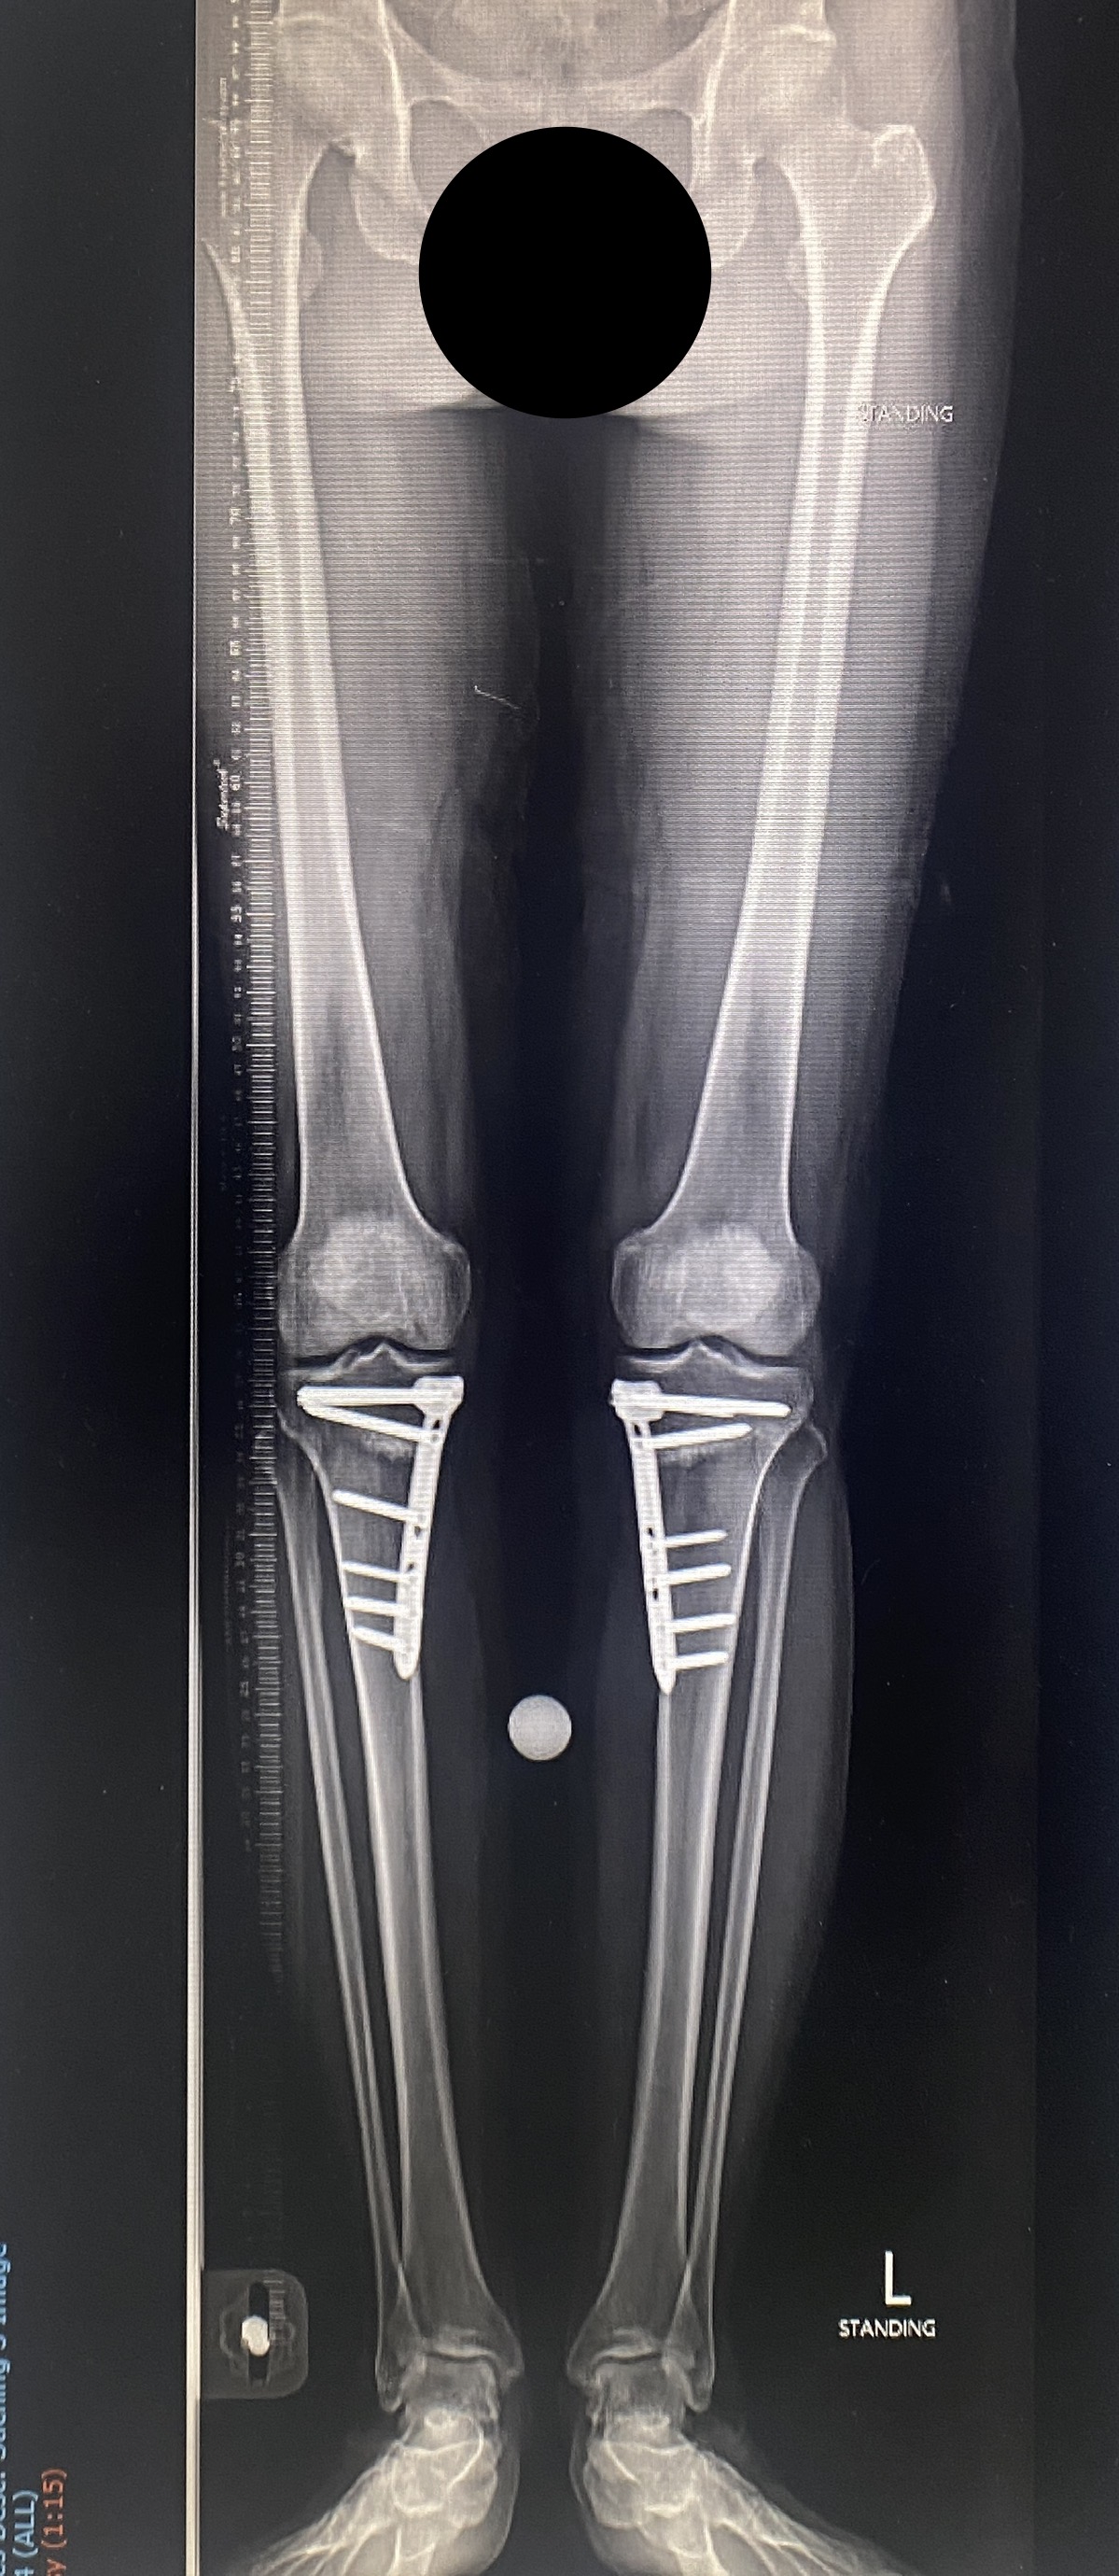

ภาพตัวอย่างผู้ที่ได้เข้ารับการผ่าตัดแก้ขาโก่ง ด้วยวิธี HTO โดยใช้ Tomofix plate

ผ่าตัดแก้ขาโก่งสองข้าง

การผ่าตัดสามารถปรับแนวกระดูกขาให้ตรงได้ โดยใช้วิธีที่เรียกว่า High tibial osteotomy หรือ HTO

เป็นมาตรฐานที่ใช้กันที่ประเทศสหรัฐอเมริกาและยุโรป คือการใช้โลหะดามชนิดแผ่น เช่น Tomofix plate (Johnson and Johnson, Synthes) เป็นต้น